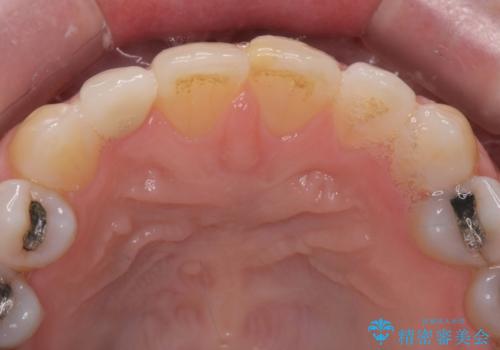

矮小(わいしょう)歯の形をセラミックで自然に 50代女性

- 右上の2番目の前歯がとがった形をしていたため、セラミックで形を整えています。

短くてとがった歯の形が反対側と同じ形となり、左右対称となり、ずいぶん自然な印象になりました。

下の前歯とのかみ合わせが切端咬合だったため、前歯の部分矯正も併せて行っています。(費用別途)